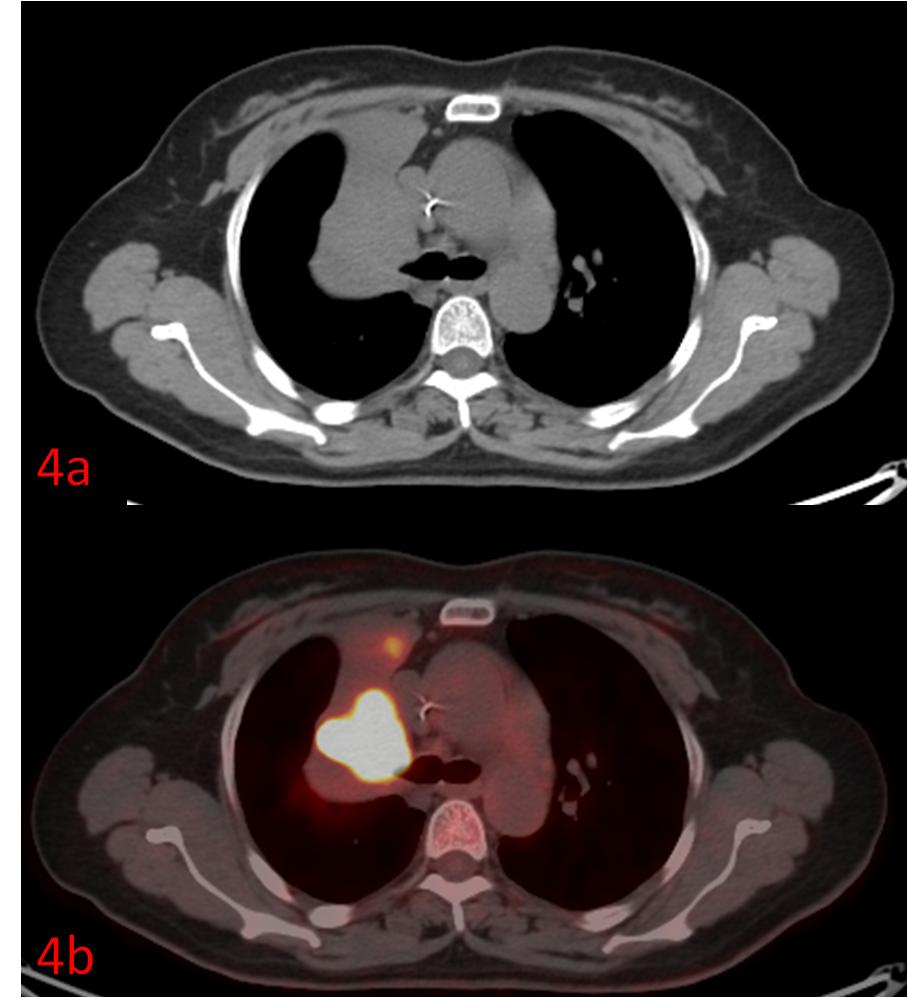

例4:中年女性,右肺上葉小細胞癌伴右肺上葉不張、阻塞性炎癥,常規CT無法區分腫瘤和不張的肺組織(圖4a),PET/CT清晰展示了腫瘤的邊界(圖4b)。